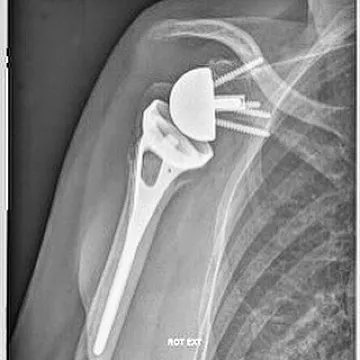

La mise en place d'une prothèse de l'épaule est indiquée si la fracture n'est pas synthésable, c'est-à-dire si les fragments osseux ne peuvent pas être remis en place. Cette prothèse permet de reconstituer l'extrémité supérieure de l'humérus et de redonner la fonction de l'épaule par l'intermédiaire des muscles intacts.

Le plus souvent une prothèse inversée est indiquée lorsqu'il existe des lésions associées des tendons de la coiffe des rotateurs ou lorsque la qualité osseuse des tubérosités est médiocre. C'est souvent le cas lors des fractures survenant chez des personnes âgées.

Une prothèse anatomique est indiquée dans certains cas lorsque les tendons de la coiffe des rotateurs sont fonctionnels et réparables (réparation des tubérosités) mais qu'il existe un risque de nécrose de la tête humérale important.

L'intervention est le plus souvent réalisée sous anesthésie loco-régionale. L'immobilisation post-opératoire est réalisée dans une attelle coude au corps. La rééducation est débutée de façon immédiate en centre de rééducation puis poursuivie en ville chez un kinésithérapeute. La durée de récupération est longue et parfois incomplète.

La mise en place d'une prothèse est indiquée lorsque la fracture est non synthésable, c'est-à-dire lorsque les fragments osseux ne peuvent pas être remis en place et fixés de façon stable. C'est notamment le cas des fractures complexes à 4 fragments chez les patients âgés. Une prothèse inversée est le plus souvent choisie lorsque la coiffe des rotateurs est également lésée ou lorsque la qualité osseuse est médiocre. (Voir Prothèse d'épaule →)